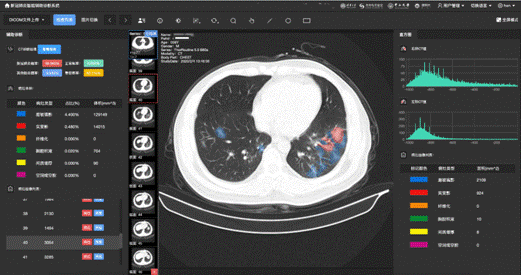

新冠肺炎影像辅助诊断应用界面

在这项工作中,科研团队采用了总计53万多张的CT影像,构建了基于病灶分割的新冠肺炎智能诊断模型。该系统可对来自新冠肺炎患者、普通肺炎患者以及对照组的CT影像数据进行区分,诊断新冠肺炎的准确率达到了92.49%(灵敏度94.93%,特异度91.13%)。利用来自不同地区的不同数据集,这套AI诊断系统经受住了真实世界研究的考验——利用大规模的回溯性数据及前瞻队列研究,该AI系统均可达到90%左右的准确率,即便是使用海外的CT数据,这套系统也达到了84.11%的准确率。在回顾性数据中,系统获得了90.70%的准确率;在前瞻队列研究中,系统在一个疫情高发区获得了91.20%准确率,在两个疫情低发地区分别获得90.32%、89.67%的准确率。这一系列研究结果表明,这套AI诊断系统无论是采用中国数据还是国际数据,都具有良好的泛化性能。

此外,通过医生手工标注的四千余张CT影像的典型病灶,系统可以对新冠肺炎、其他病毒性肺炎及细菌性肺炎的五类典型病灶(磨玻璃影、实变、空腔空洞等)自动进行精准定位,通过精准分析每一个病灶的大小和变化,可以作为药物筛选检测临床试验的判别标准。